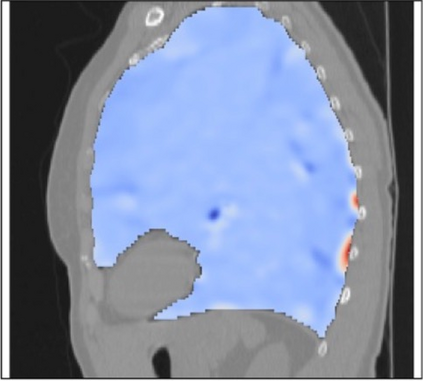

Deformable image registration is a fundamental task in medical image analysis and plays a crucial role in a wide range of clinical applications. Recently, deep learning-based approaches have been widely studied for deformable medical image registration and achieved promising results. However, existing deep learning image registration techniques do not theoretically guarantee topology-preserving transformations. This is a key property to preserve anatomical structures and achieve plausible transformations that can be used in real clinical settings. We propose a novel framework for deformable image registration. Firstly, we introduce a novel regulariser based on conformal-invariant properties in a nonlinear elasticity setting. Our regulariser enforces the deformation field to be smooth, invertible and orientation-preserving. More importantly, we strictly guarantee topology preservation yielding to a clinical meaningful registration. Secondly, we boost the performance of our regulariser through coordinate MLPs, where one can view the to-be-registered images as continuously differentiable entities. We demonstrate, through numerical and visual experiments, that our framework is able to outperform current techniques for image registration.